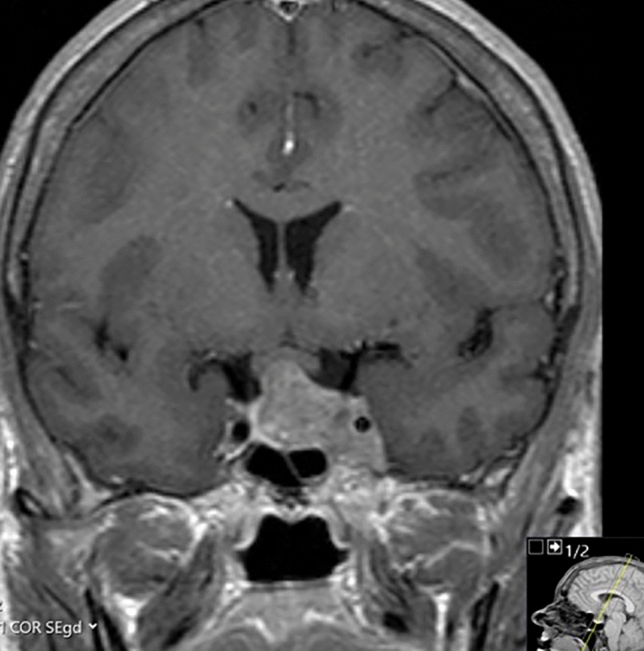

At the time of diagnosis, laboratory results showed significantly elevated growth hormone (GH; random 43.90 mU/L, and nadir following glucose suppression test 16.20 mU/L (reference range 0.00–7.25 mU/L) and insulin-like growth factor-1 (IGF-1) levels of 96.3 nmol/L (1.3 × upper limit of normal (ULN), reference range 7.0–76.0 nmol/L), and insufficient corticotropic, gonadotropic and thyrotropic axes. The pituitary MRI scan revealed a macroadenoma with invasion of the left cavernous sinus hampering total resection, as shown in Fig. 1. Cardiac examination showed left ventricular hypertrophy with mild diastolic dysfunction, and a moderate mitral and tricuspid valve insufficiency, whilst colonoscopy showed multiple colonic polyps with low grade dysplasia: all presumably complications of longstanding (undiagnosed) GH excess.

Fig. 1.

Magnetic resonance imaging of the sellar region. In 2008, the diagnostic coronal T1-weighted magnetic resonance image of the sellar region after intravenous administration of contrast revealed a macroadenoma with invasion of the left cavernous sinus and some compression of the optic chiasm